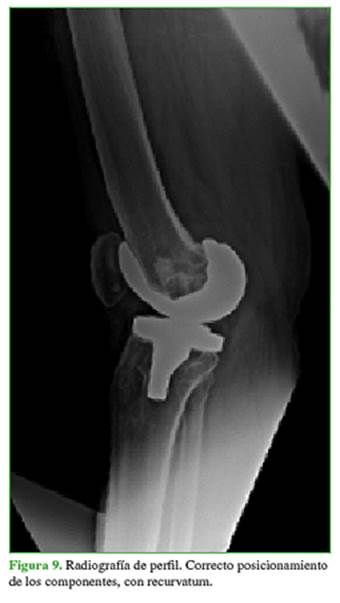

Concurrió a nuestro centro en marzo de 2016 (aproximadamente 2 años después de la intervención) por inestabilidad de la prótesis en recurvatum que le impedía la marcha; no refirió un antecedente traumático (Figuras 8 y 9).

En abril de 2016, se procedió a la revisión de la prótesis y se colocó una prótesis abisagrada rotatoria Endo-Model®. La paciente ha tenido una buena evolución hasta la fecha (34 meses poscirugía) (Figuras 10 y 11).